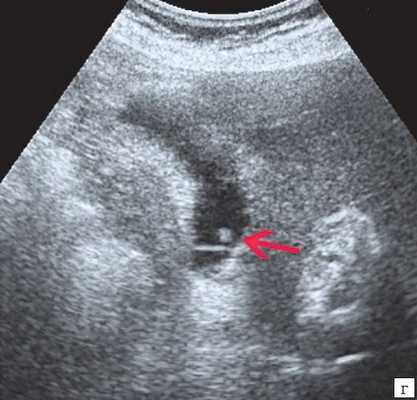

(Левый) Положение пациента на боку. На продольном УЗ срезе визуализируется смещающийся книзу под действием гравитации эхогенный сладж, формирующий сгусток.

(Правый) На продольном УЗ срезе у этого же пациента в положении на боку определяется смещающийся книзу под действием гравитации эхогенный сладж, также виден «мерцающий» артефакт.